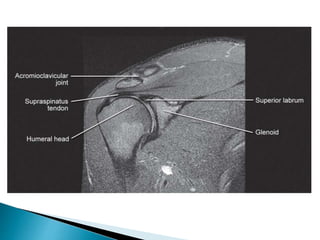

• 30.

 Shoulder – ◦Rotator cuff tear ◦ Impingement syndromes ◦ Instability ◦ Osteonecrosis ◦ Pathological conditions of the tendon  Spine – ◦ Evaluation of intervertebral disk disease ◦ Discitis ◦ Pyogenic and tuberculous infections